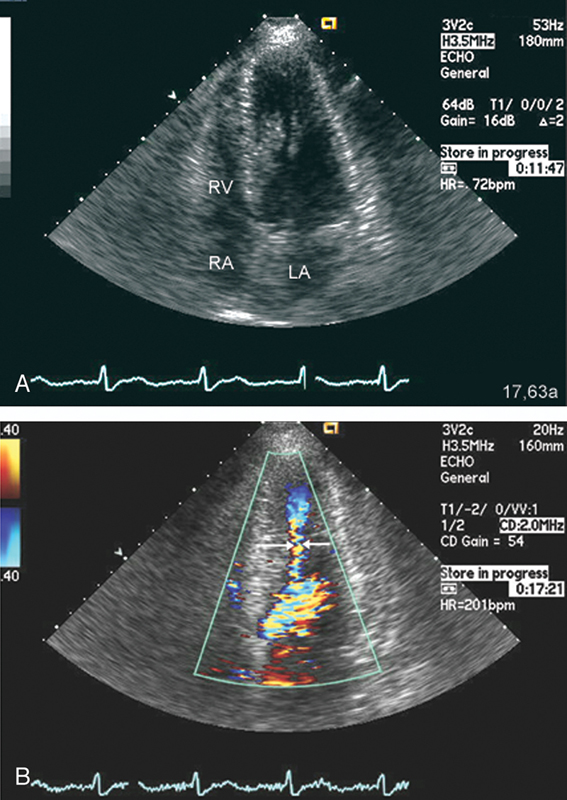

فحوصات تشخيصية لبعض امراض القلب والشرايين التاجية